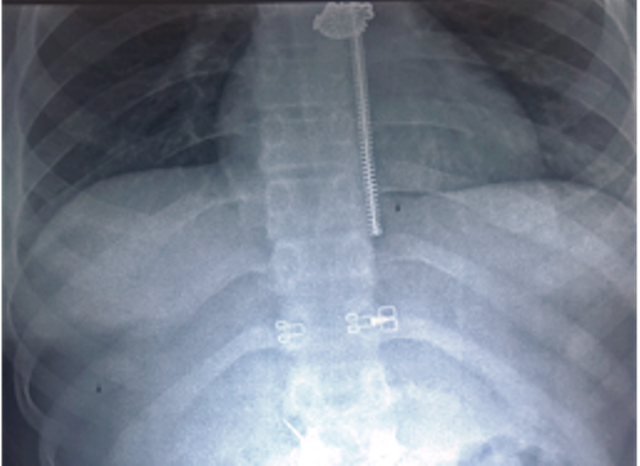

| Hình ảnh kim thêu trong bụng bệnh nhân. Ảnh bệnh viện cung cấp |

Sau đó bệnh nhân được chuyển sang BV Đa khoa Cần Thơ trong tình trạng đau bụng vùng thượng vị. Bác sĩ Nguyễn Nghiêm Minh, trưởng phòng kế hoạch tổng hợp cho biết sau khi khám lâm sàng và chụp X-Quang tim phổi, bụng các bác sĩ phát hiện dị vật cản quang là một cây kim một đầu nhọn, một đầu có bọc nhựa dài khoảng 2cm.